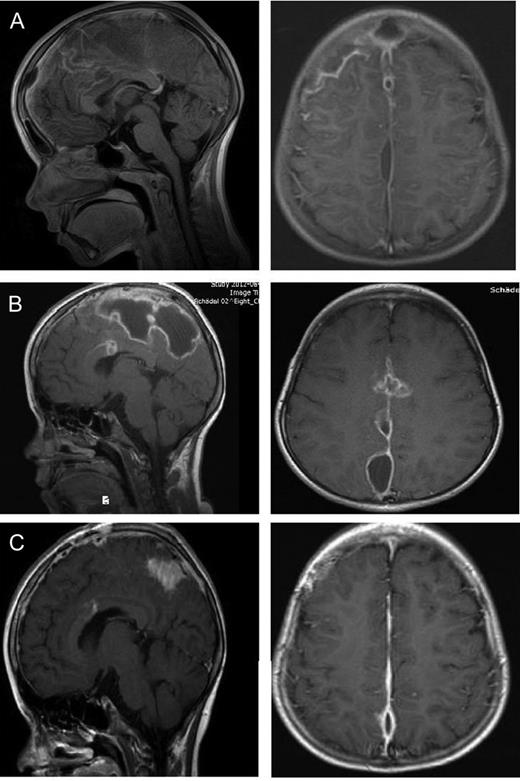

An 8-year-old girl with a diagnosed sinusitis frontalis, already under antibiotic therapy, developed progressive headaches and increasing infection parameters. The brain MRI showed a subdural frontal parafalcine empyema (Fig. 2A). The girl's symptoms were nausea, emesis, headache and fever but no neurological disturbance. We drained the empyema by a right frontal craniotomy and clear the abscess cavity with isotonic saline solution. The brain extended rapidly after removing the space-occupying pus. Microbiologically, streptococcus intermedius infection was verified. The antibiotic therapy was optimized after resistogram. After surgery, the girl's condition got worse with seizures and fever. In a repeated MRI (Fig. 2B), the subdural empyema showed an enlargement. We decided to revise and extend the approach to remove the capsule of the empyema which could be seen perioperatively. The empyema was released by an osteoplastic right parasagittal trepanation.

Eight-year-old girl with parafalcine subdural empyema. (A) Axial and sagittal MRI section with administration of gadolinium. Space occupying empyema with the largest expansion right frontal and contact to the falx. Perifocal edema without a significant midline shift is seen. (B) Axial and sagittal MRI section with administration of gadolinium. An enlargement of the empyema is visible after first surgery. The empyema is localized in central parasagittal region with a significant space-occupying component with a compression of the right central region. (C) Axial and sagittal MRI section with administration of gadolinium. A regression is visible after second surgery. In comparison to preoperative MRI, a notable decrease in the space-occupying part of the empyema is seen.

The symptomatic epilepsy was treated with levetiracetam. Afterwards, the girl stayed for another week in our department. At the day of discharge, an MRI (Fig. 2C) was repeated and showed a regressive parafalcine abscess. The infection parameters decrease steadily under antibiotics and no seizures were noticed anymore. An MRI was performed 3 months after second surgery. After the last MRI, the antibiotic and the antiepileptic therapy were stopped.